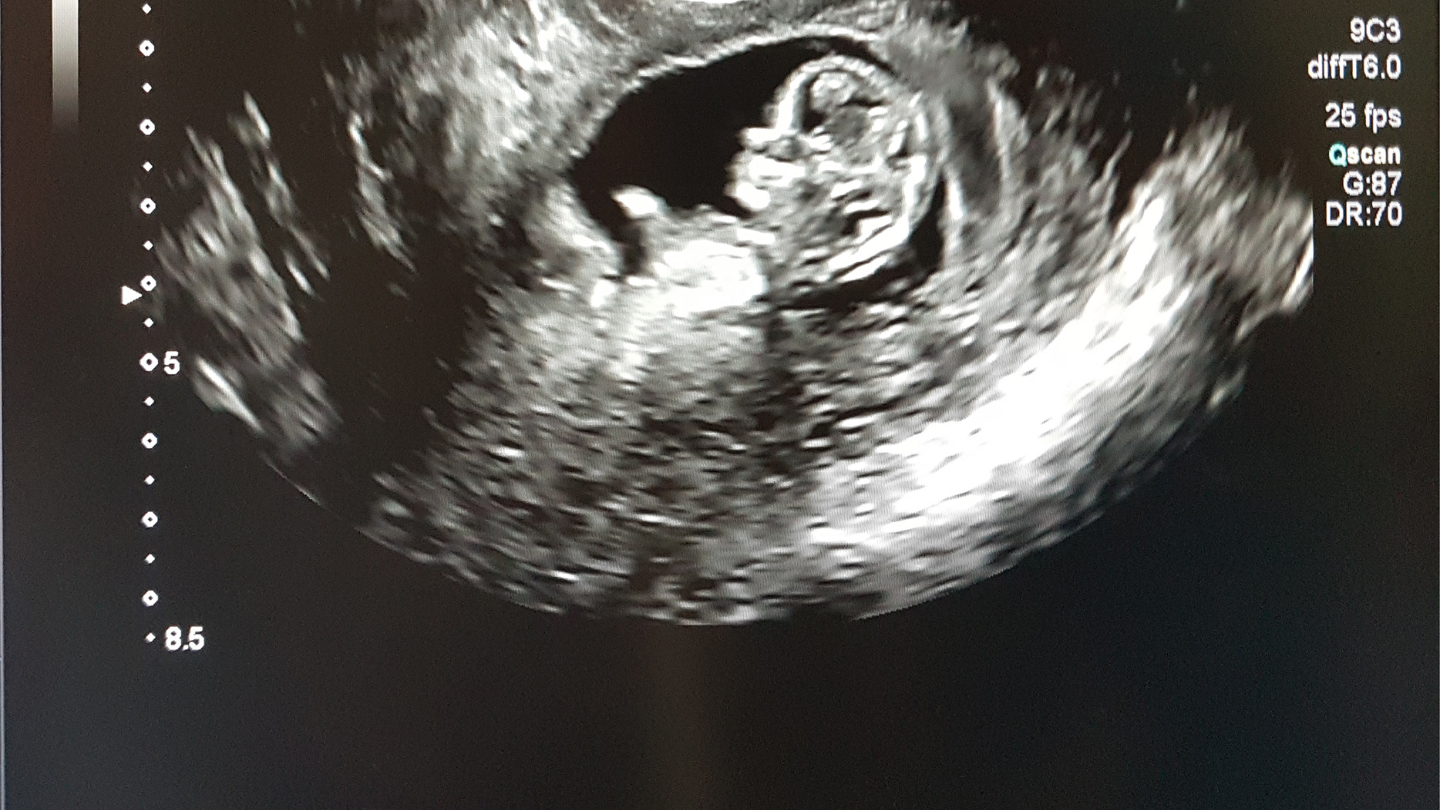

Chi phí làm xét nghiệm sàng lọc 3 tháng đầu phụ thuộc vào loại phương pháp bạn chọn. Nhìn chung, các xét nghiệm cơ bản có giá phải chăng, trong khi các phương pháp cao cấp hơn sẽ tốn kém hơn. Trong 3 tháng đầu (thường từ tuần 11 – 13), xét nghiệm sàng lọc phổ biến nhất là Double Test, kết hợp xét nghiệm sinh hóa máu và siêu âm đo độ mờ da gáy (NT). Đây là bước đầu tiên giúp đánh giá nguy cơ hội chứng Down, Edwards và Patau ở thai nhi.

Double Test là xét nghiệm phổ biến nhất trong xét nghiệm sàng lọc 3 tháng đầu, thực hiện từ tuần 11 - 13 + 6 (tức là gần tròn 14 tuần), nhằm sàng lọc hội chứng Down (trisomy 21), Edwards (trisomy 18) và Patau (trisomy 13). Quy trình bao gồm lấy máu mẹ đo nồng độ beta-hCG tự do và PAPP-A, kết hợp siêu âm đo độ mờ da gáy (NT) và chiều dài đầu - mông thai nhi.

Siêu âm NT là kỹ thuật đo lớp dịch sau gáy thai nhi (từ tuần 11 - 13 + 6), kết hợp xét nghiệm máu cơ bản (như công thức máu, tuyến giáp) để đánh giá nguy cơ dị tật. Đây là nền tảng cho Double Test và các gói sàng lọc khác. Đây là phần thiết yếu trong xét nghiệm sàng lọc 3 tháng đầu, thường kết hợp với máu để tăng độ chính xác lên 90%.